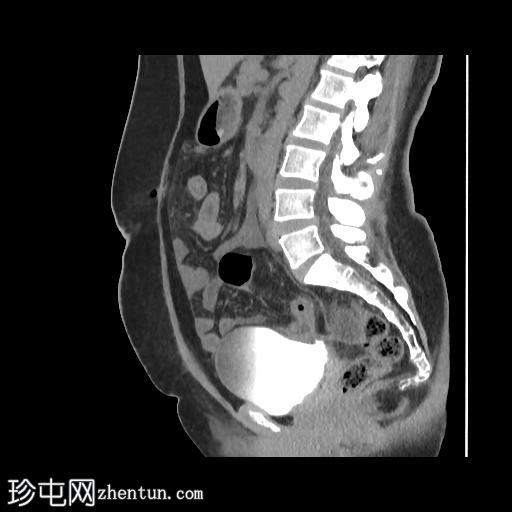

矢状位增强扫描(门静脉期)

CT扫描显示:

左侧膀胱后外侧壁完全撕裂,造影剂外渗至盆腔

盆腔内可见少量积液

腹膜脂肪条索状改变,腹膜反折增厚强化,提示盆腔腹膜炎

腹腔镜

子宫切除术后医源性膀胱损伤伴盆腔腹膜炎的CT表现。